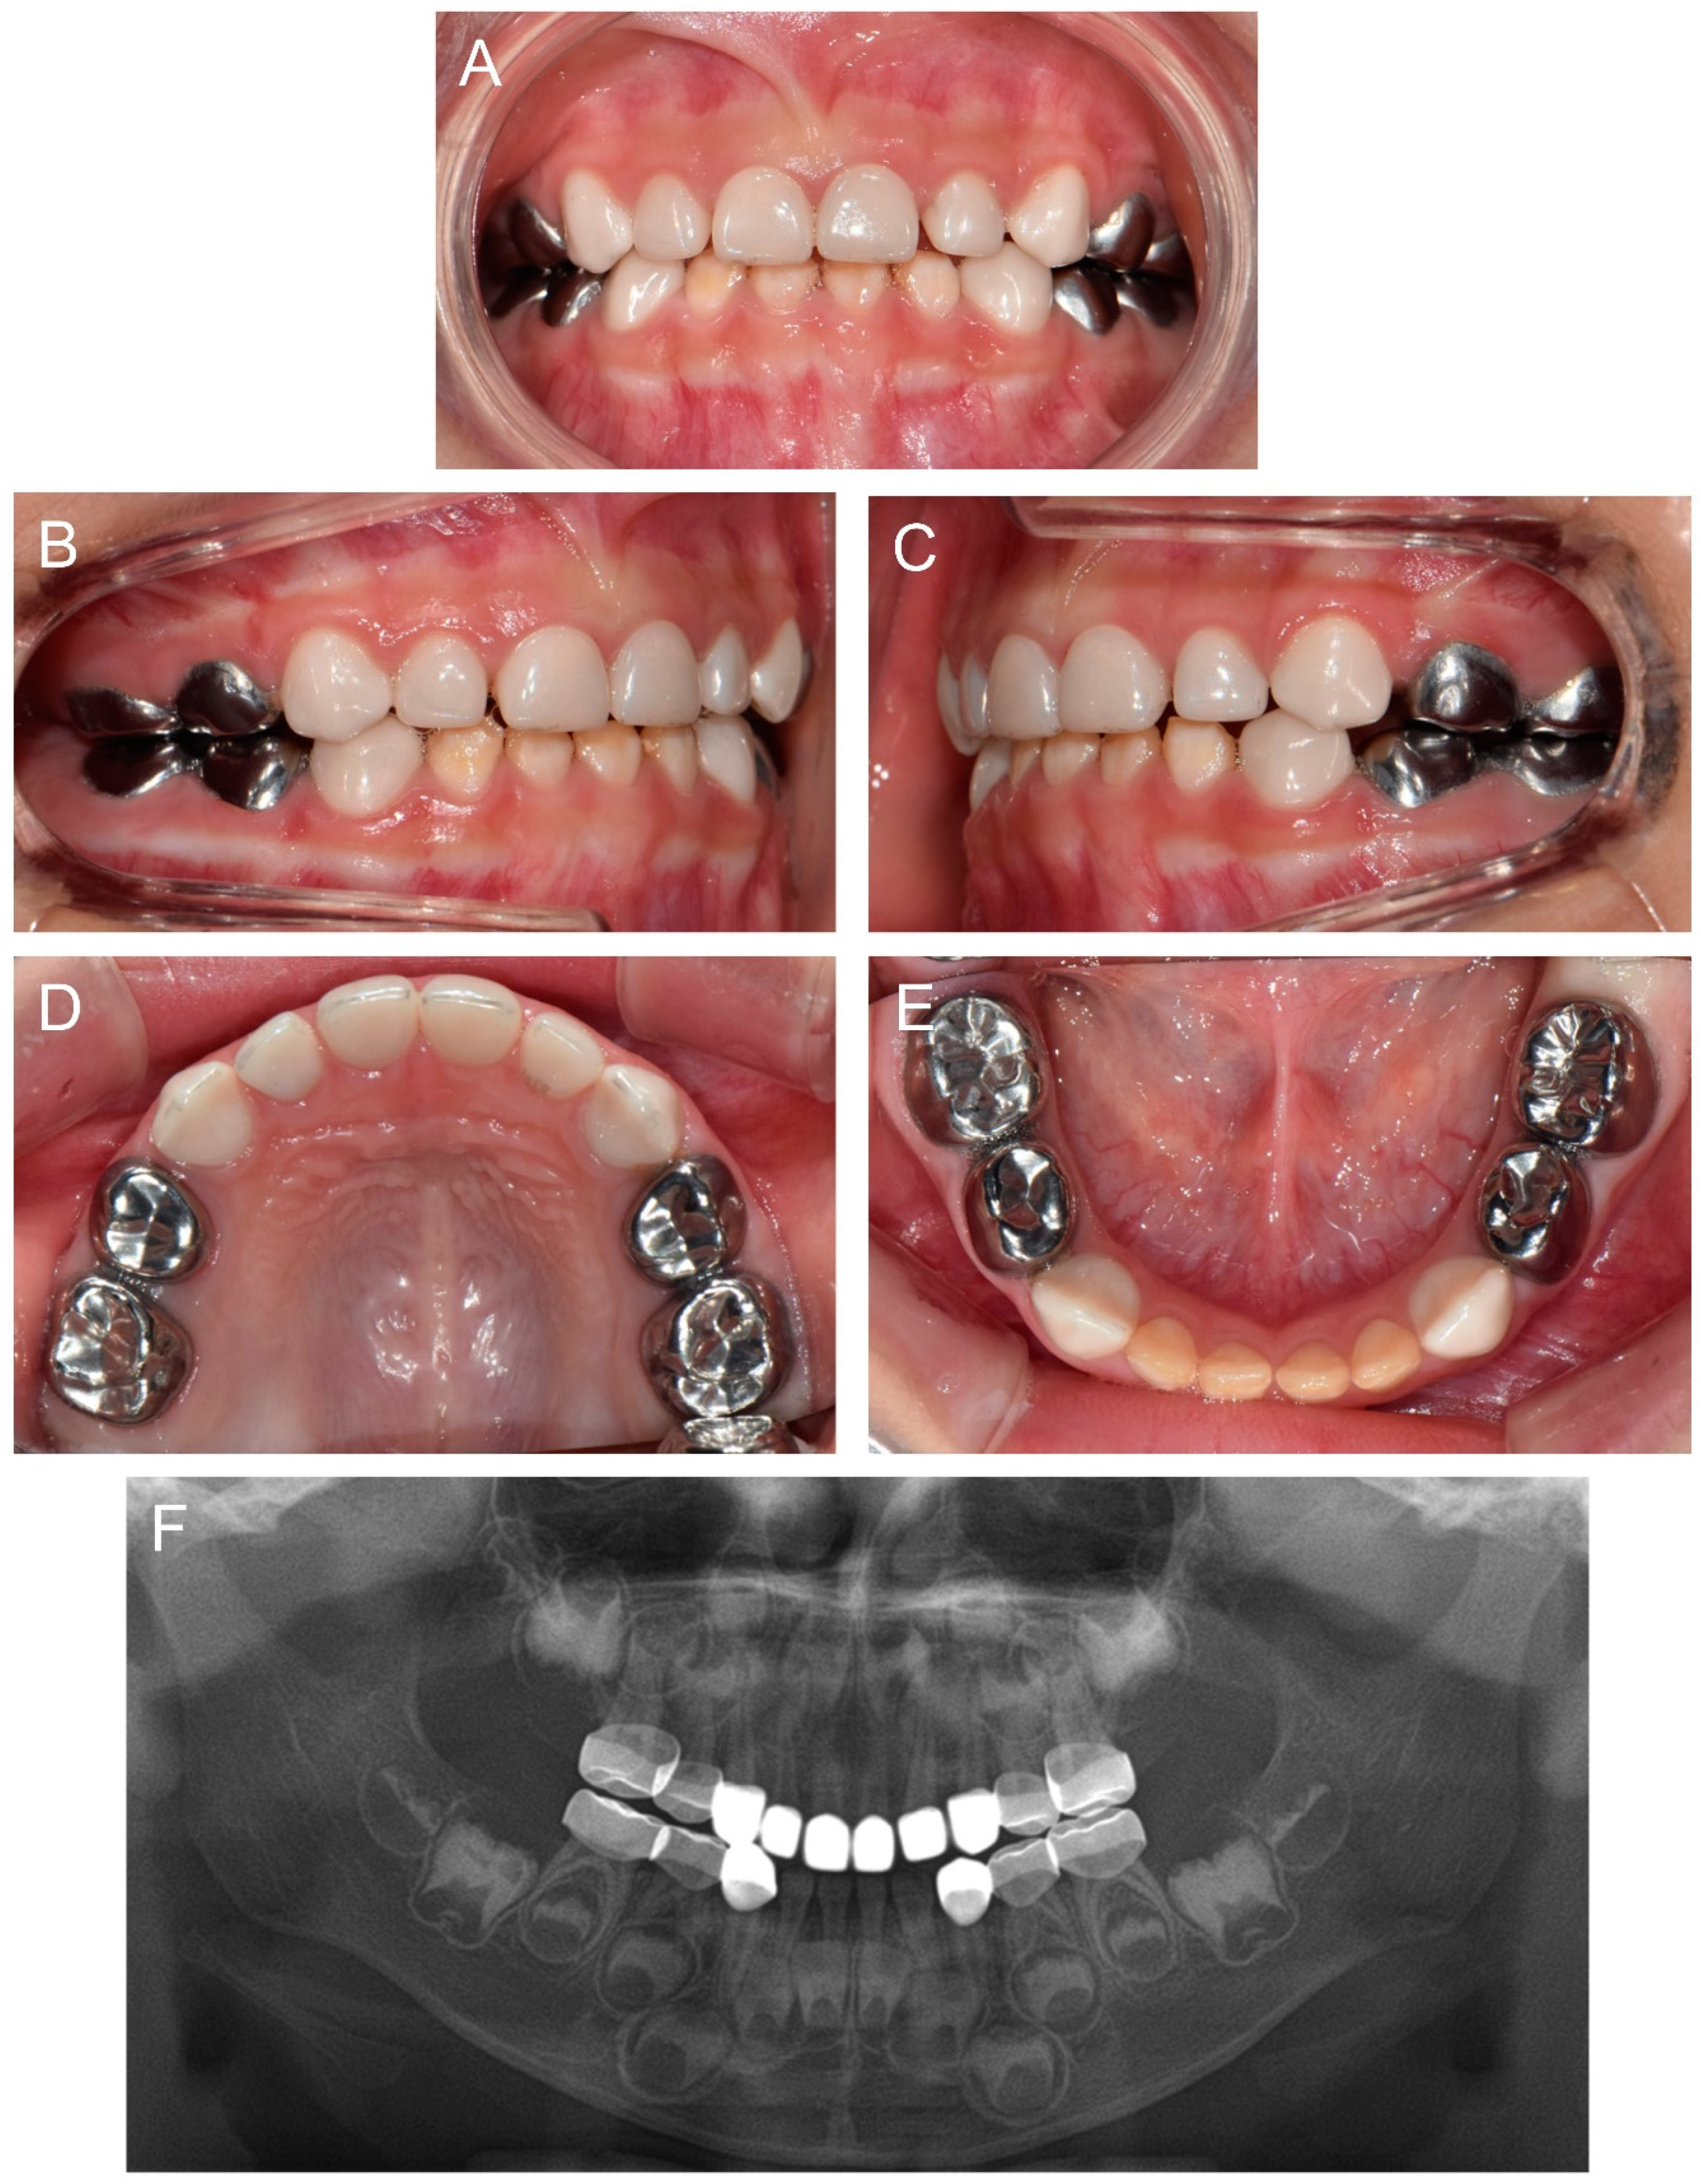

At 2Y9M, full-mouth restoration was performed under outpatient GA (Figure 2). Deciduous molars were treated with stainless steel crowns. Deciduous canines and maxillary anterior teeth were treated with zirconia crowns. Deciduous mandibular anterior teeth were left untreated. At the 3Y11M follow-up (Figure 3), good oral health was maintained, and the anterior open bite was spontaneously corrected with the discontinuance of the finger sucking habit.

Figure 2.

Clinical photos of the proband (IV:3). (A–D) Clinical photos of the proband before the treatment at age 2 years 9 months. (E–H) Clinical photos of the proband after the treatment. The deciduous molars were treated with stainless steel crowns, and the deciduous canines and maxillary anterior teeth were treated with zirconia crowns. The deciduous mandibular anterior teeth were left untreated.

Figure 3.

Clinical photos and panoramic radiograph of the proband at age 3 years 11 months. (A–E) Oral health and restorations were well maintained. Anterior open bite was spontaneously corrected with the discontinuance of the finger sucking habit. (F) Panoramic radiograph showed hypocalcified enamel in the developing permanent teeth.